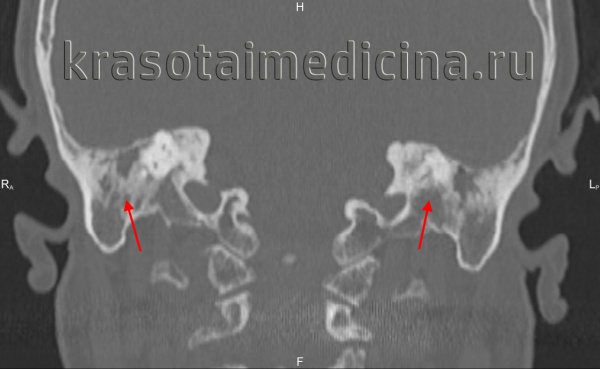

КТ височных костей. С обеих сторон диффузное снижение пневматизации ячеек сосцевидного отростка и пирамиды височной кости за счет отосклероза